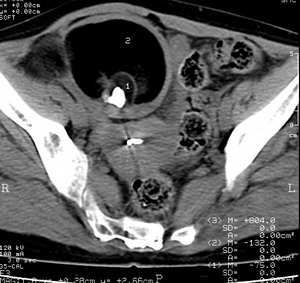

女、50岁右下腹痛二年余查右下腹稍膨隆、局部压痛。考虑:畸胎瘤并肉芽增殖性腹膜炎,不排除恶性变

右下腹混杂密度影,还是考虑畸胎瘤吧

脂肪密度+钙化。畸胎瘤应该没问题吧?

成熟型畸胎瘤恶变可能大

依据1腹腔积液2肿块巨大形态不规则、密度不均匀与周周有粘连

腹腔积液2肿块巨大形态不规则、密度不均匀与周周有粘连之低等混杂影,且见钙化。考虑畸胎瘤,并提示恶变可能。

畸胎瘤起源于外,内,中三个胚层,为实质性,常有大小不等的囊性区域,囊性者多为良性,囊壁为纤维组织,易钙化,囊内含有皮脂样液体。组织结构可包含脂肪、毛发、骨与软骨、牙齿等。肿瘤较小时患者多无自觉症状,较大者对组织与器官产生压迫症状。有文献分析40%平片可发现囊壁钙化、肿块中含牙齿和骨结构而明确诊断,但由于ct检查的密度分辨率更高,更易发现脂质、钙化、骨及牙齿等结构,而成为诊断畸胎瘤最特异的方法。如ct上既没有见到脂肪密度,也没有见到钙化的囊性肿块就不能诊断为畸胎瘤。ct检查中必须测定囊性肿块中不同密度组织的ct值,以辨别是否含有脂肪组织,如有脂肪一液体平面时,可改变体位扫描,低密度的脂肪成分必然始终飘浮在上方。盆腔非脏器起源的畸胎瘤常发生在骶骨前区、恶性畸胎瘤占有一定比例,这时脂肪钙化或骨化成分较少,常破坏骶骨并侵犯邻近脏器者,与其它恶变较难鉴别。

子宫右前方巨大囊性混杂密度影,囊内以脂肪密度为主,并见斑点状高密度钙化,壁较厚且均匀,支持卵巢囊性畸胎瘤。